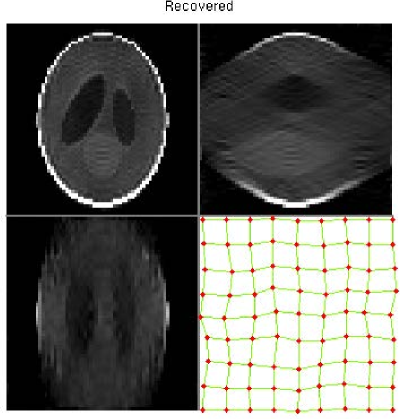

For the B-spline transformation model, we initially use a 3D Shepp-Logan phantom to test our simultaneous method. Figure 15(a) shows the 3D Shepp-Logan phantom (65×65×6565656565\times 65\times 65 in voxels), and also shows the central slice of each plane and the regular B-spline control point grid for the central slice of the transverse plane. The transformed phantom is shown in Figure 15(b), and illustrates the ground truth of the transformation. This ground truth deformation is simulated with the B-spline transformation model using 9×9×99999\times 9\times 9 control points randomly offset in each dimension.

In this experiment, we set different ranges of perturbation for each direction (x-, y- and z-axis), e.g., [Rangea,Rangeb]=[8,8]subscriptRangeasubscriptRangeb88[\mathrm{Range}_{\mathrm{a}},\mathrm{Range}_{\mathrm{b}}]=[-8,8], =[4,4]absent44=[-4,4], and =[2,2]absent22=[-2,2] (voxels) have been used respectively. Therefore, there are larger deformations for the in-plane slices and smaller ones for the out-of-plane. From the results shown in Figures 16(a) and (b), we can conclude that our simultaneous method has obtained an accurate reconstruction with a reasonable recovery of the non-rigid deformations. The montage views of the fixed, transformed, recovered, and difference images are shown in Figures 19, 20, 21, and 22.

Refer to caption

Figure 15: (a): Original fixed 3D Shepp-Logan phantom and its regular grid for the central slice; (b): Transformed 3D Shepp-Logan phantom and its deformed grid for the central slice, i.e., ground truth of the transformation. (Four sub-figures from top to bottom and from left to right are: Transverse view; Coronal view; Sagittal view; Grid of the central slice of the transverse view.)

Figure 16: (a): Simultaneous reconstruction and registration result and the registered control point grid for the central slice; (b): Difference image between the simultaneous result and the original fixed phantom. The registered control point grid is superimposed on the ground truth transformation and indicates that the ground truth transformation has been recovered well for the majority of control points.

The third investigation evaluated incorporating a non-rigid transformation model into our combined framework (Section 6.3). In particular, we employed the B-spline transformation model and tested it with our simultaneous method. Results generated using a 3D Shepp-Logan phantom image offer compelling evidence that our simultaneous method has successfully reconstructed the volume with accurate recovery of the non-rigid deformations.